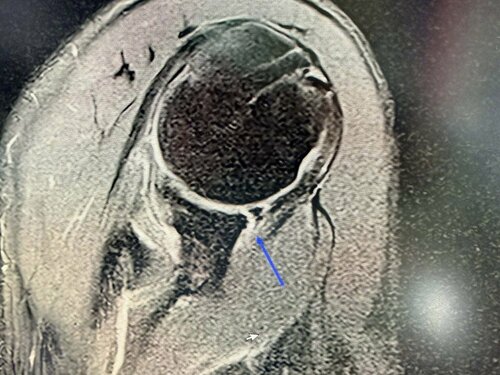

後日医院を訪れて診断結果を聞くと、「腱板部分断裂および関節唇損傷」とのこと。肩の腱が半分切れて、関節の縁も傷んでいる。「結構な重症よ。サーフィンはしばらく禁止。これ以上切れたら手術だからね」と容赦がありません。

まずは痛みを取らなければなりません。エコーガイド下でステロイド注射。キシロカインとデカドロン。こちらは保険適用なので比較的安価。これでしばらく様子を見ます。